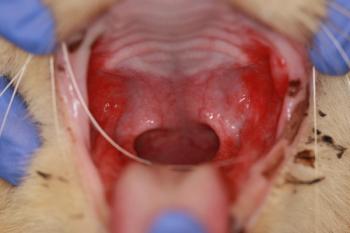

The investigational trial will evaluate the safety, efficacy, and potency of using stem cells to treat cats with refractory gingivostomatitis.

Test your diagnostic skills by examining the following images and selecting the answer you think fits best.